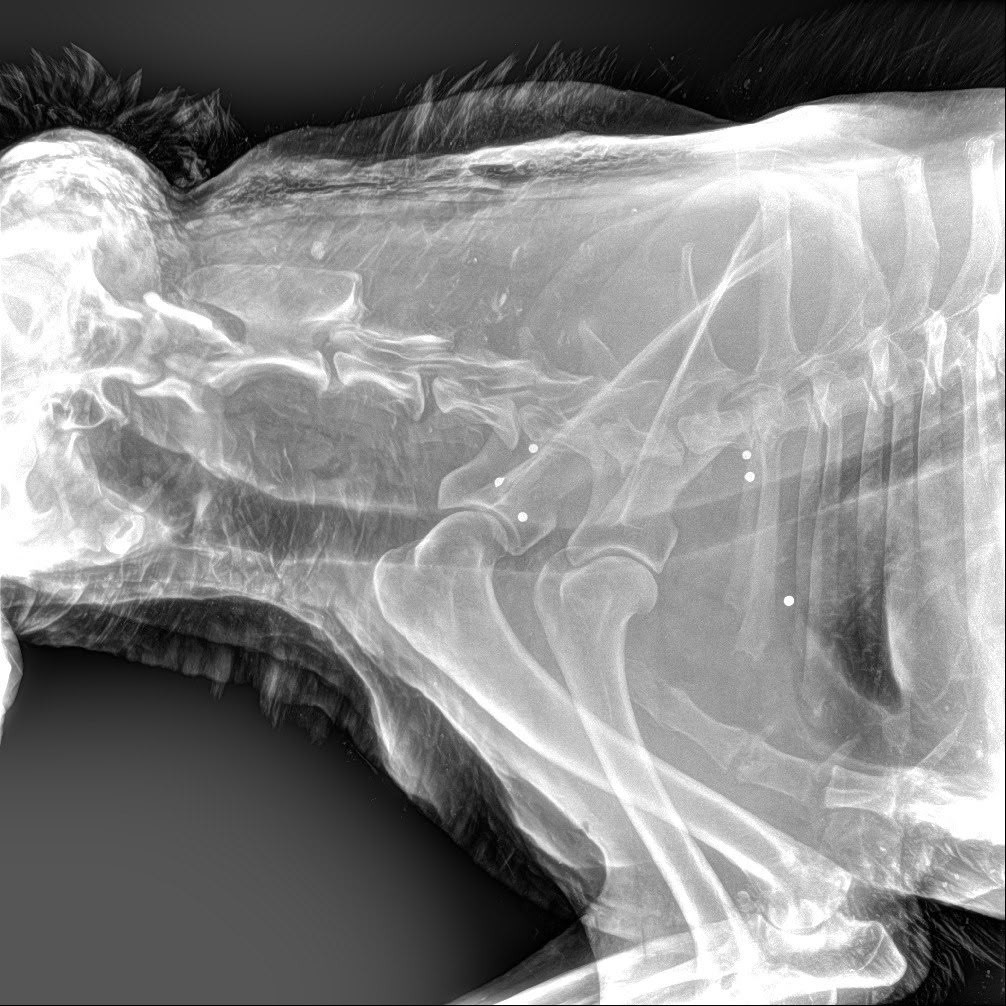

Животное доставили в ветклинику в Красное Село. Как рассказал 47news директор фонда Сергей Лучинский, при обследовании выяснилось, что в собаку стреляли. Рентген показал больше 30 шариков, крайне похожих на ружейную дробь. Раны есть даже на голове. Кроме того, волонтеры предполагают, что собаку мог сбить автомобиль.